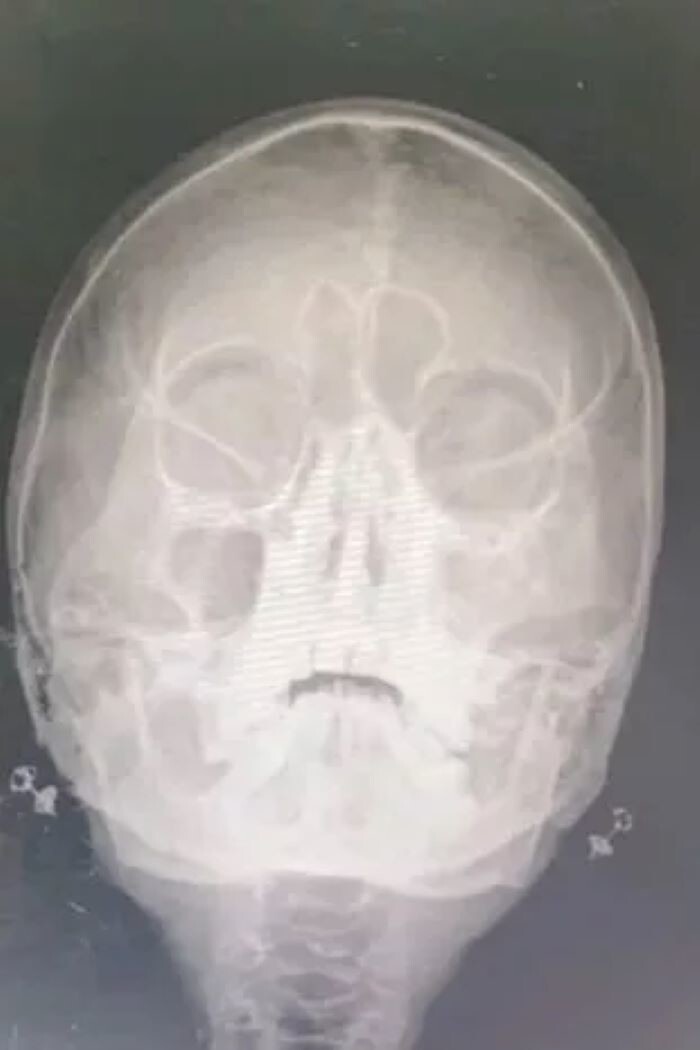

She immediately went for examination to the hospital in Nakornping (Chiang Mai province, northern Thailand). Dr. Pateemon Thanachaihan examined the X-ray and noticed foreign bodies in the nostrils.